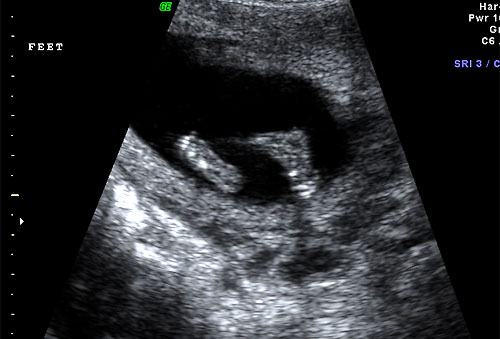

Normal 16 week fetal feet |